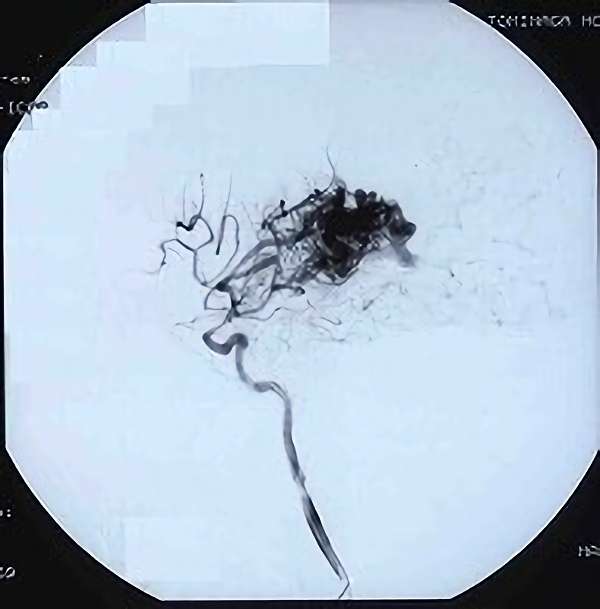

'19年5月

30代

富永/久貝

右中小脳脚 出血再発

SM 3(S1,E1,V1)

米国の病院

No.359 モニタリング

No.359 手術前

No.359 手術中

No.359 手術後

出血既往があり。2回の手術前血管内手術の後に、

Lateral transpeduncular approachにより再々出血予防を目的に

摘出手術を行う。完全摘出であることを確認した。

手術による合併症や後遺症なしで退院した。経過良好。